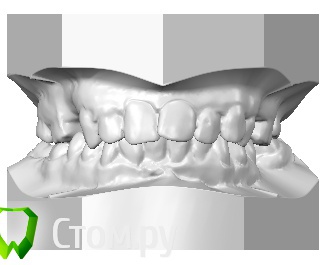

2,5 года прохожу ортодонтическое лечение на брекетах  системы Виктори ( металлических)., в последствии буду протезироваться на имплантах

У меня есть  сомнения насчет результата лечения,в частности я недовольная овалом лица и нижней челюстью.

Прилагаю все имеющиеся снимки ( до и сейчас) и фото данный момент.

2-смущает окклюзионная плоскость на нижней челюсти.

4-Так же стоит обратить внимание на изменения в суставе, возможно стоит дообследоваться, опять же, по ОПТГ об этом не судят, но изменения есть, скорее всего это связано с отсутствием моляров. Проблемы с ассиметричным положением нижней челюсти решаться, с исправлением окклюзионнй плоскости, и восстановлением межальвеолярной высоты.